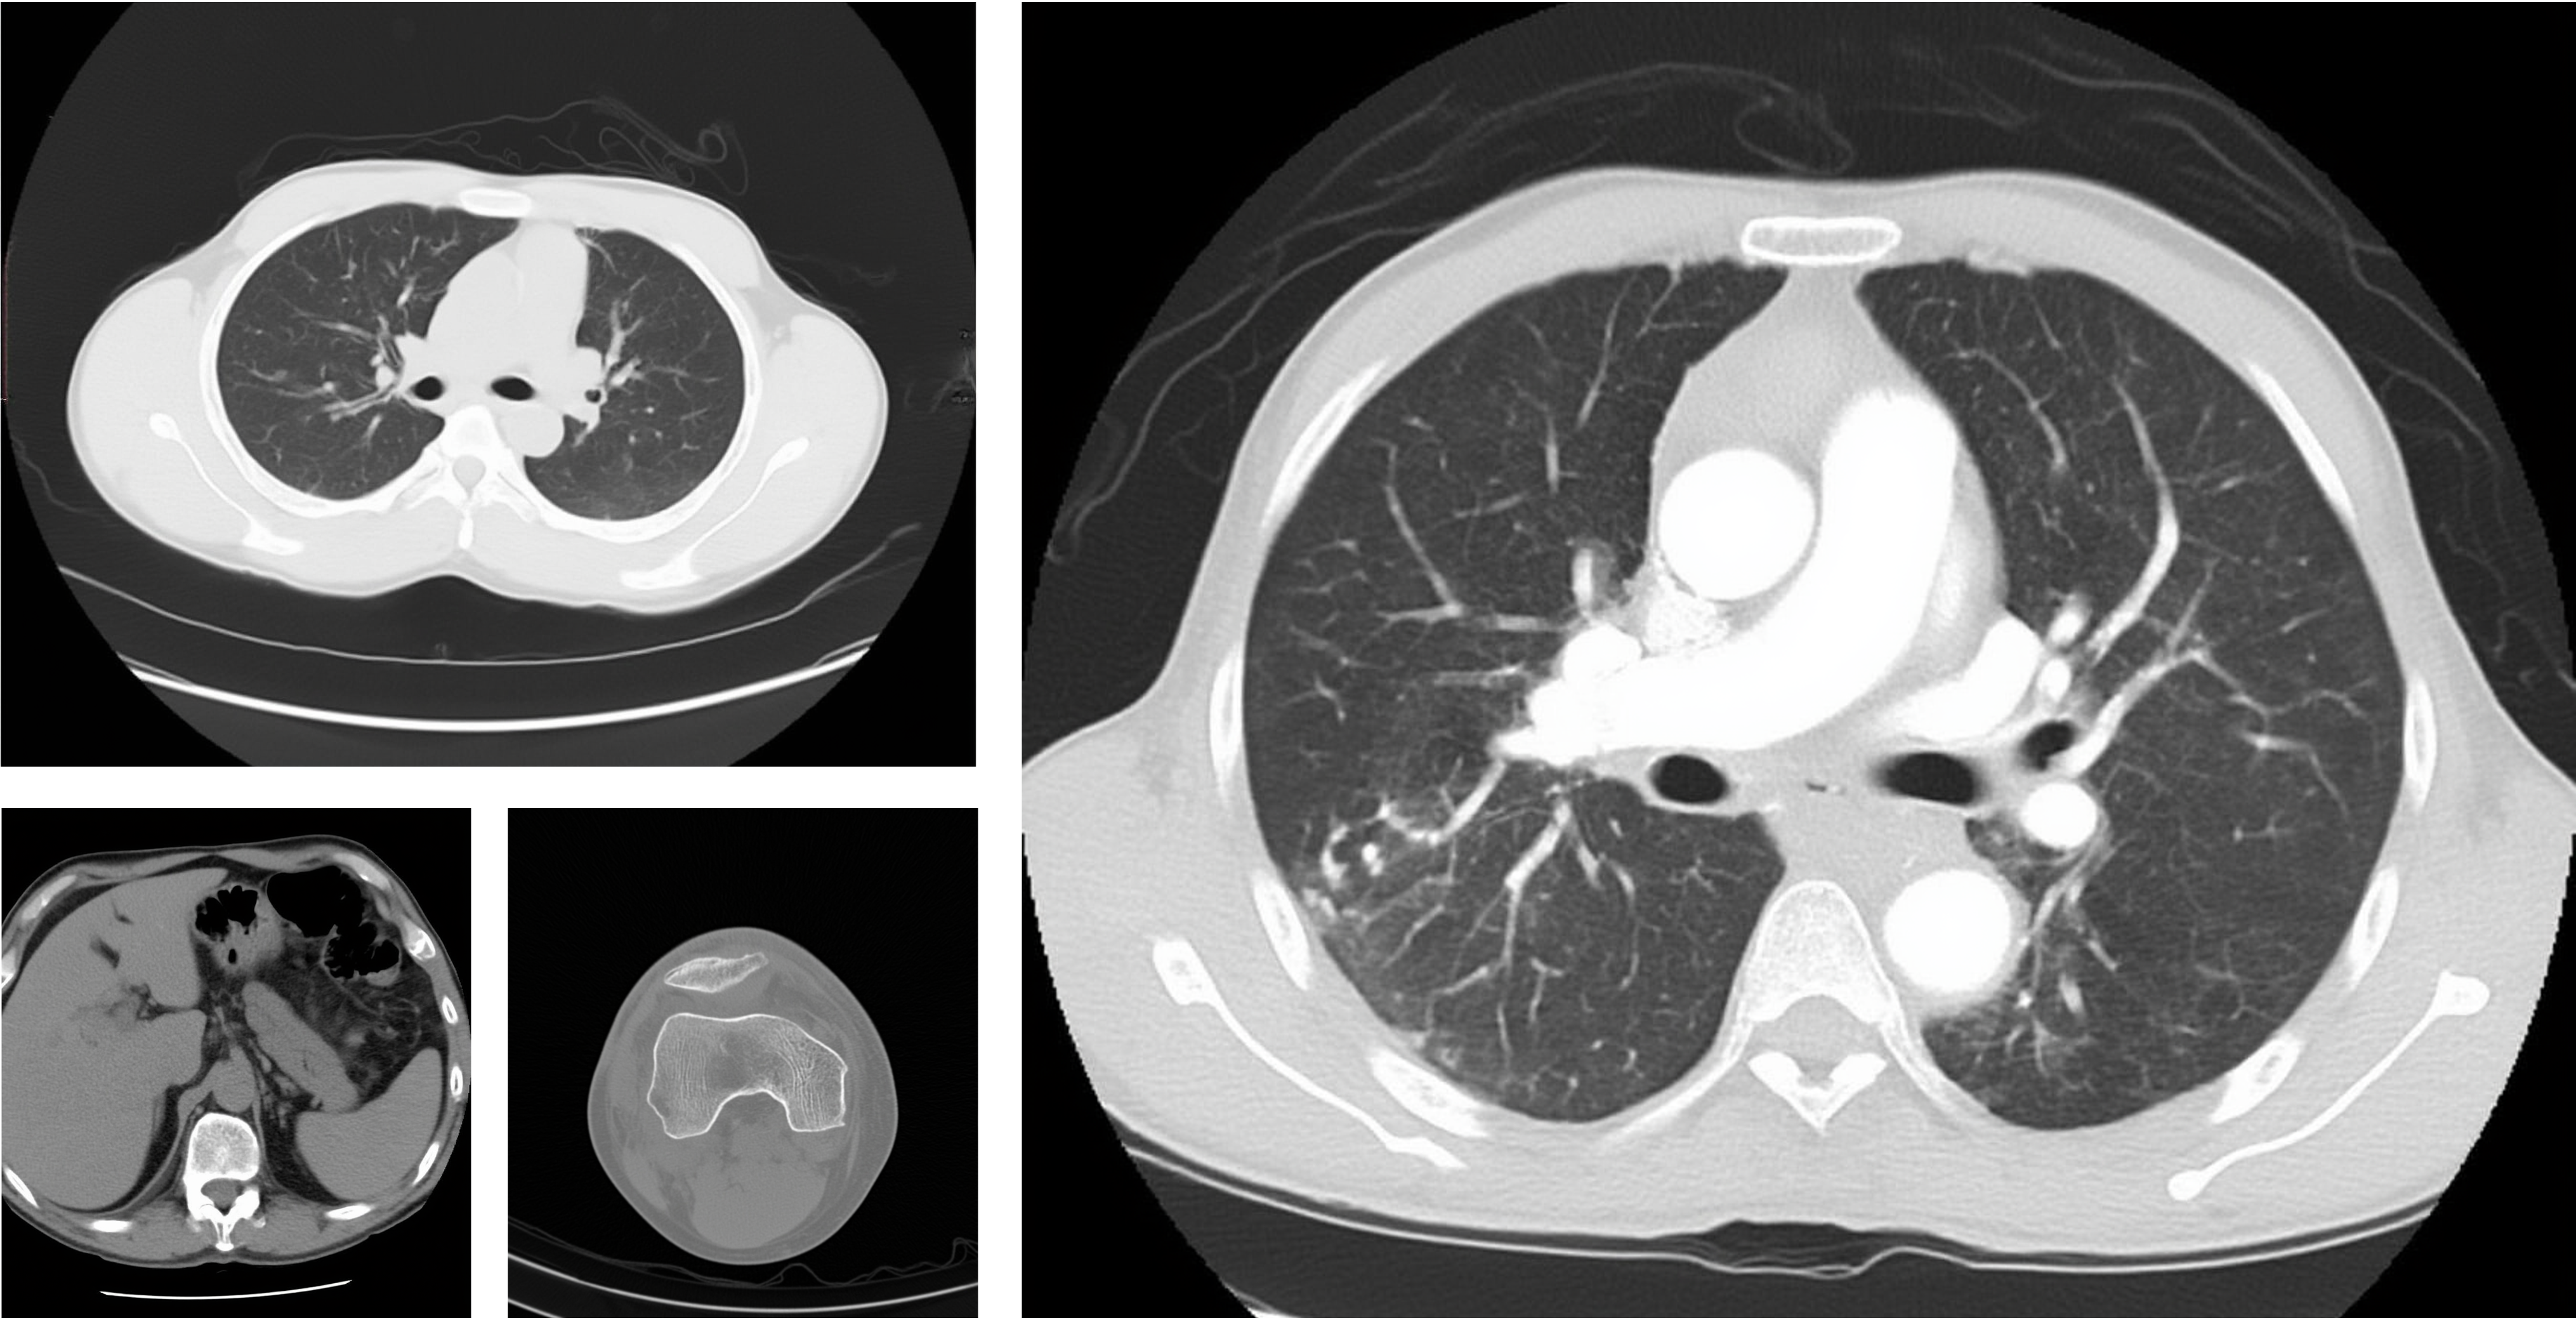

Computed Tomography (CT)

CT Scan

Magnetic Resonance Imaging (MRI)

MRI Scan